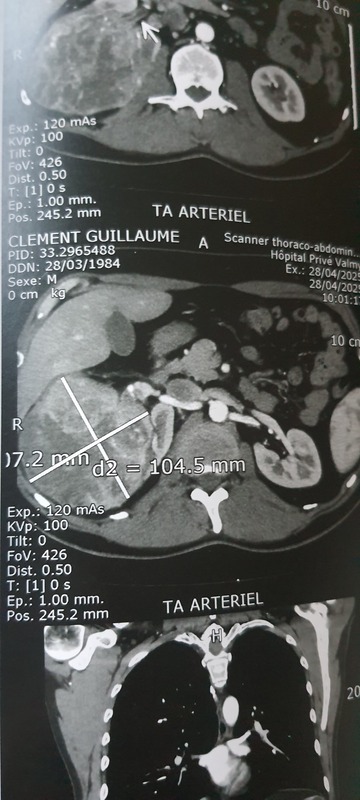

Suite à l’échographie, une masse d’environ 10 cm de diamètre a été détectée au niveau du rein, on m’a donc fait faire un scanner en urgence pour confirmer le diagnostic.

Une fois le scanner réalisé, on m’a dit qu’il faudra très certainement enlever le rein droit et consulter mon médecin traitant pour avoir un rendez-vous avec un urologue en urgence. Je pense que le but était que je comprenne que la situation était grave (pour être sûr que je m’en occupe). On ne m’a pas parlé de cancer explicitement, mais c’est bien de ça qu’on parle.

À gauche on voit le rein droit, qui aurait dû ressembler à l'autre, donc à une noix de cajou et pas à un melon